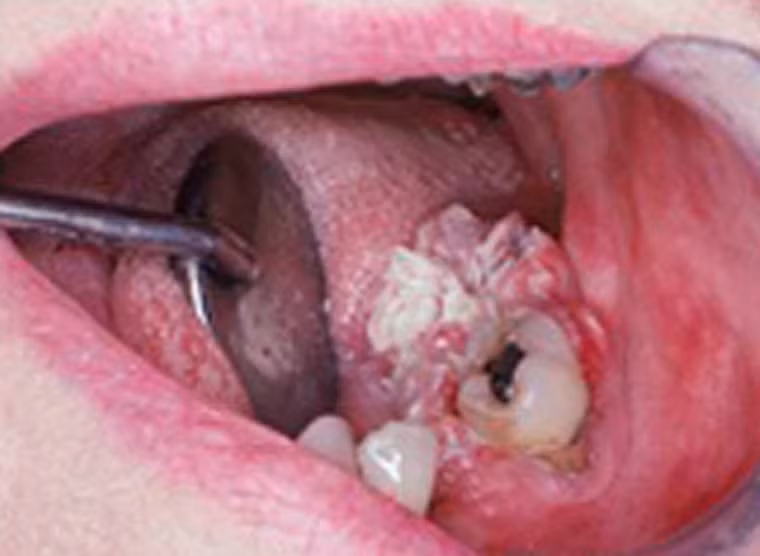

Hình ảnh cận cảnh ghi lại khối u ung thư Verrucous ở người phụ nữ 59 tuổi. Khối u không gây đau xuất hiện ngay cạnh một chiếc răng ở hàm dưới.